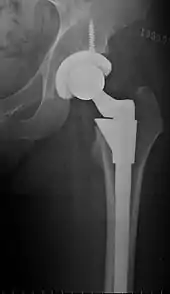

Hemiarthroplasty

Hemiarthroplasty is a surgical procedure which replaces one half of the joint with an artificial surface and leaves the other part in its natural (pre-operative) state. This class of procedure is most commonly performed on the hip after an intracapsular fracture of the neck of the femur (a hip fracture). The procedure is performed by removing the head of the femur and replacing it with a metal or composite prosthesis. The most commonly used prosthesis designs are the Austin Moore prosthesis and the Thompson Prosthesis. More recently a composite of metal and HDPE which forms two interphases (bipolar prosthesis) has also been used. The monopolar prosthesis has not been shown to have any advantage over bipolar designs. The procedure is recommended only for elderly and frail patients, due to their lower life expectancy and activity level. This is because with the passage of time the prosthesis tends to loosen or to erode the acetabulum.[75] Independently mobile older adults with hip fractures may benefit from a total hip replacement instead of hemiarthroplasty.[76]

Hip prosthesis for hemiarthroplasty. This example is bipolar, meaning that the head has two separate articulations.

X-ray of the hips, with a right-sided hemiarthroplasty.